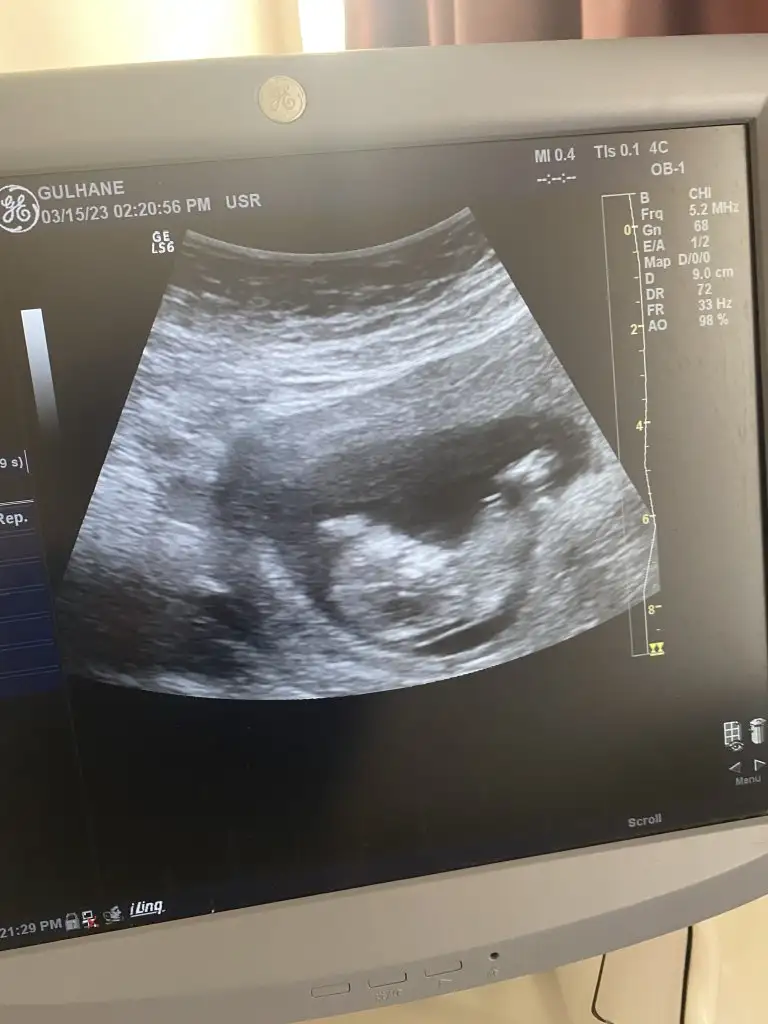

Merhabalar 12 haftalık bebeğim cinsiyet tahmini yapan varmı acaba

Eklentiler

• IMG_20221128_104000.webp

25 KB · Görüntüleme: 301